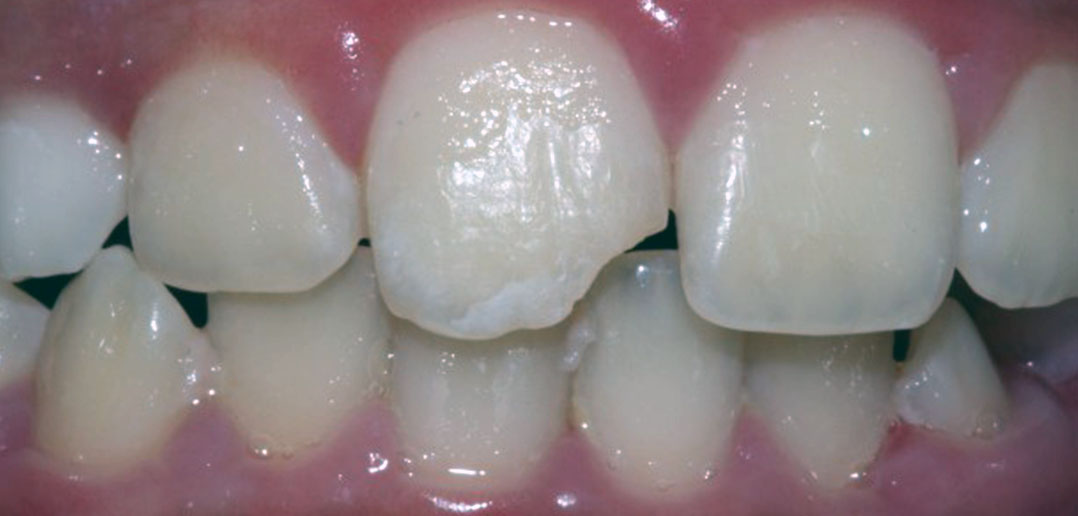

From www.styleitaliano.org

Immediate provisional restoration of a complete crown fracture Tooth Fracture X Ray Dental fractures are often clinically apparent but can be overlooked in cases with associated facial fractures, especially as root. Dental trauma is commonly classified as 1,2: Radiographic examination is essential to identify the location and extension of the fracture. Mandibular fractures represent two thirds of all maxillofacial fractures. Odontoid process fracture, also known as a peg or dens fracture, occurs. Tooth Fracture X Ray.